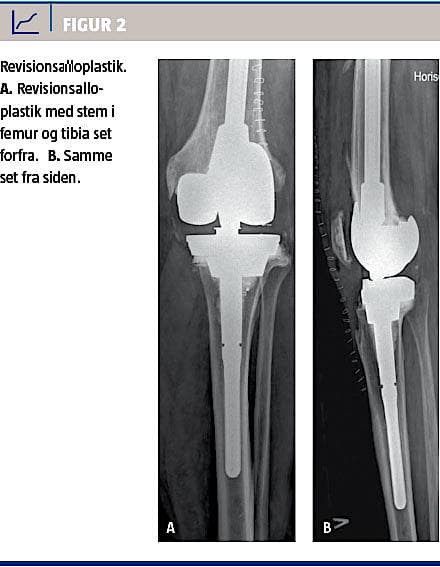

Moderne revisionssystemer er modulære, således at protesen kan opbygges i forhold til tab af knogle og ledbånd, og ledlinjen kan genskabes [25, 27]. Et stort knogletab (metafysært) kan i dag håndteres med specielle proteser [28, 29]. Alternativer til revision er bandagering (instabilitet og smerter), artrodese (manglende funktion af strækkeapparatet), og ved infektion anvendes livslang supprimerende antibiotika eller femuramputation [30]. Figur 2 viser revisionsalloplastik (roterende hængselknæ med tibiaaugmentation og trabekulær metalcone).